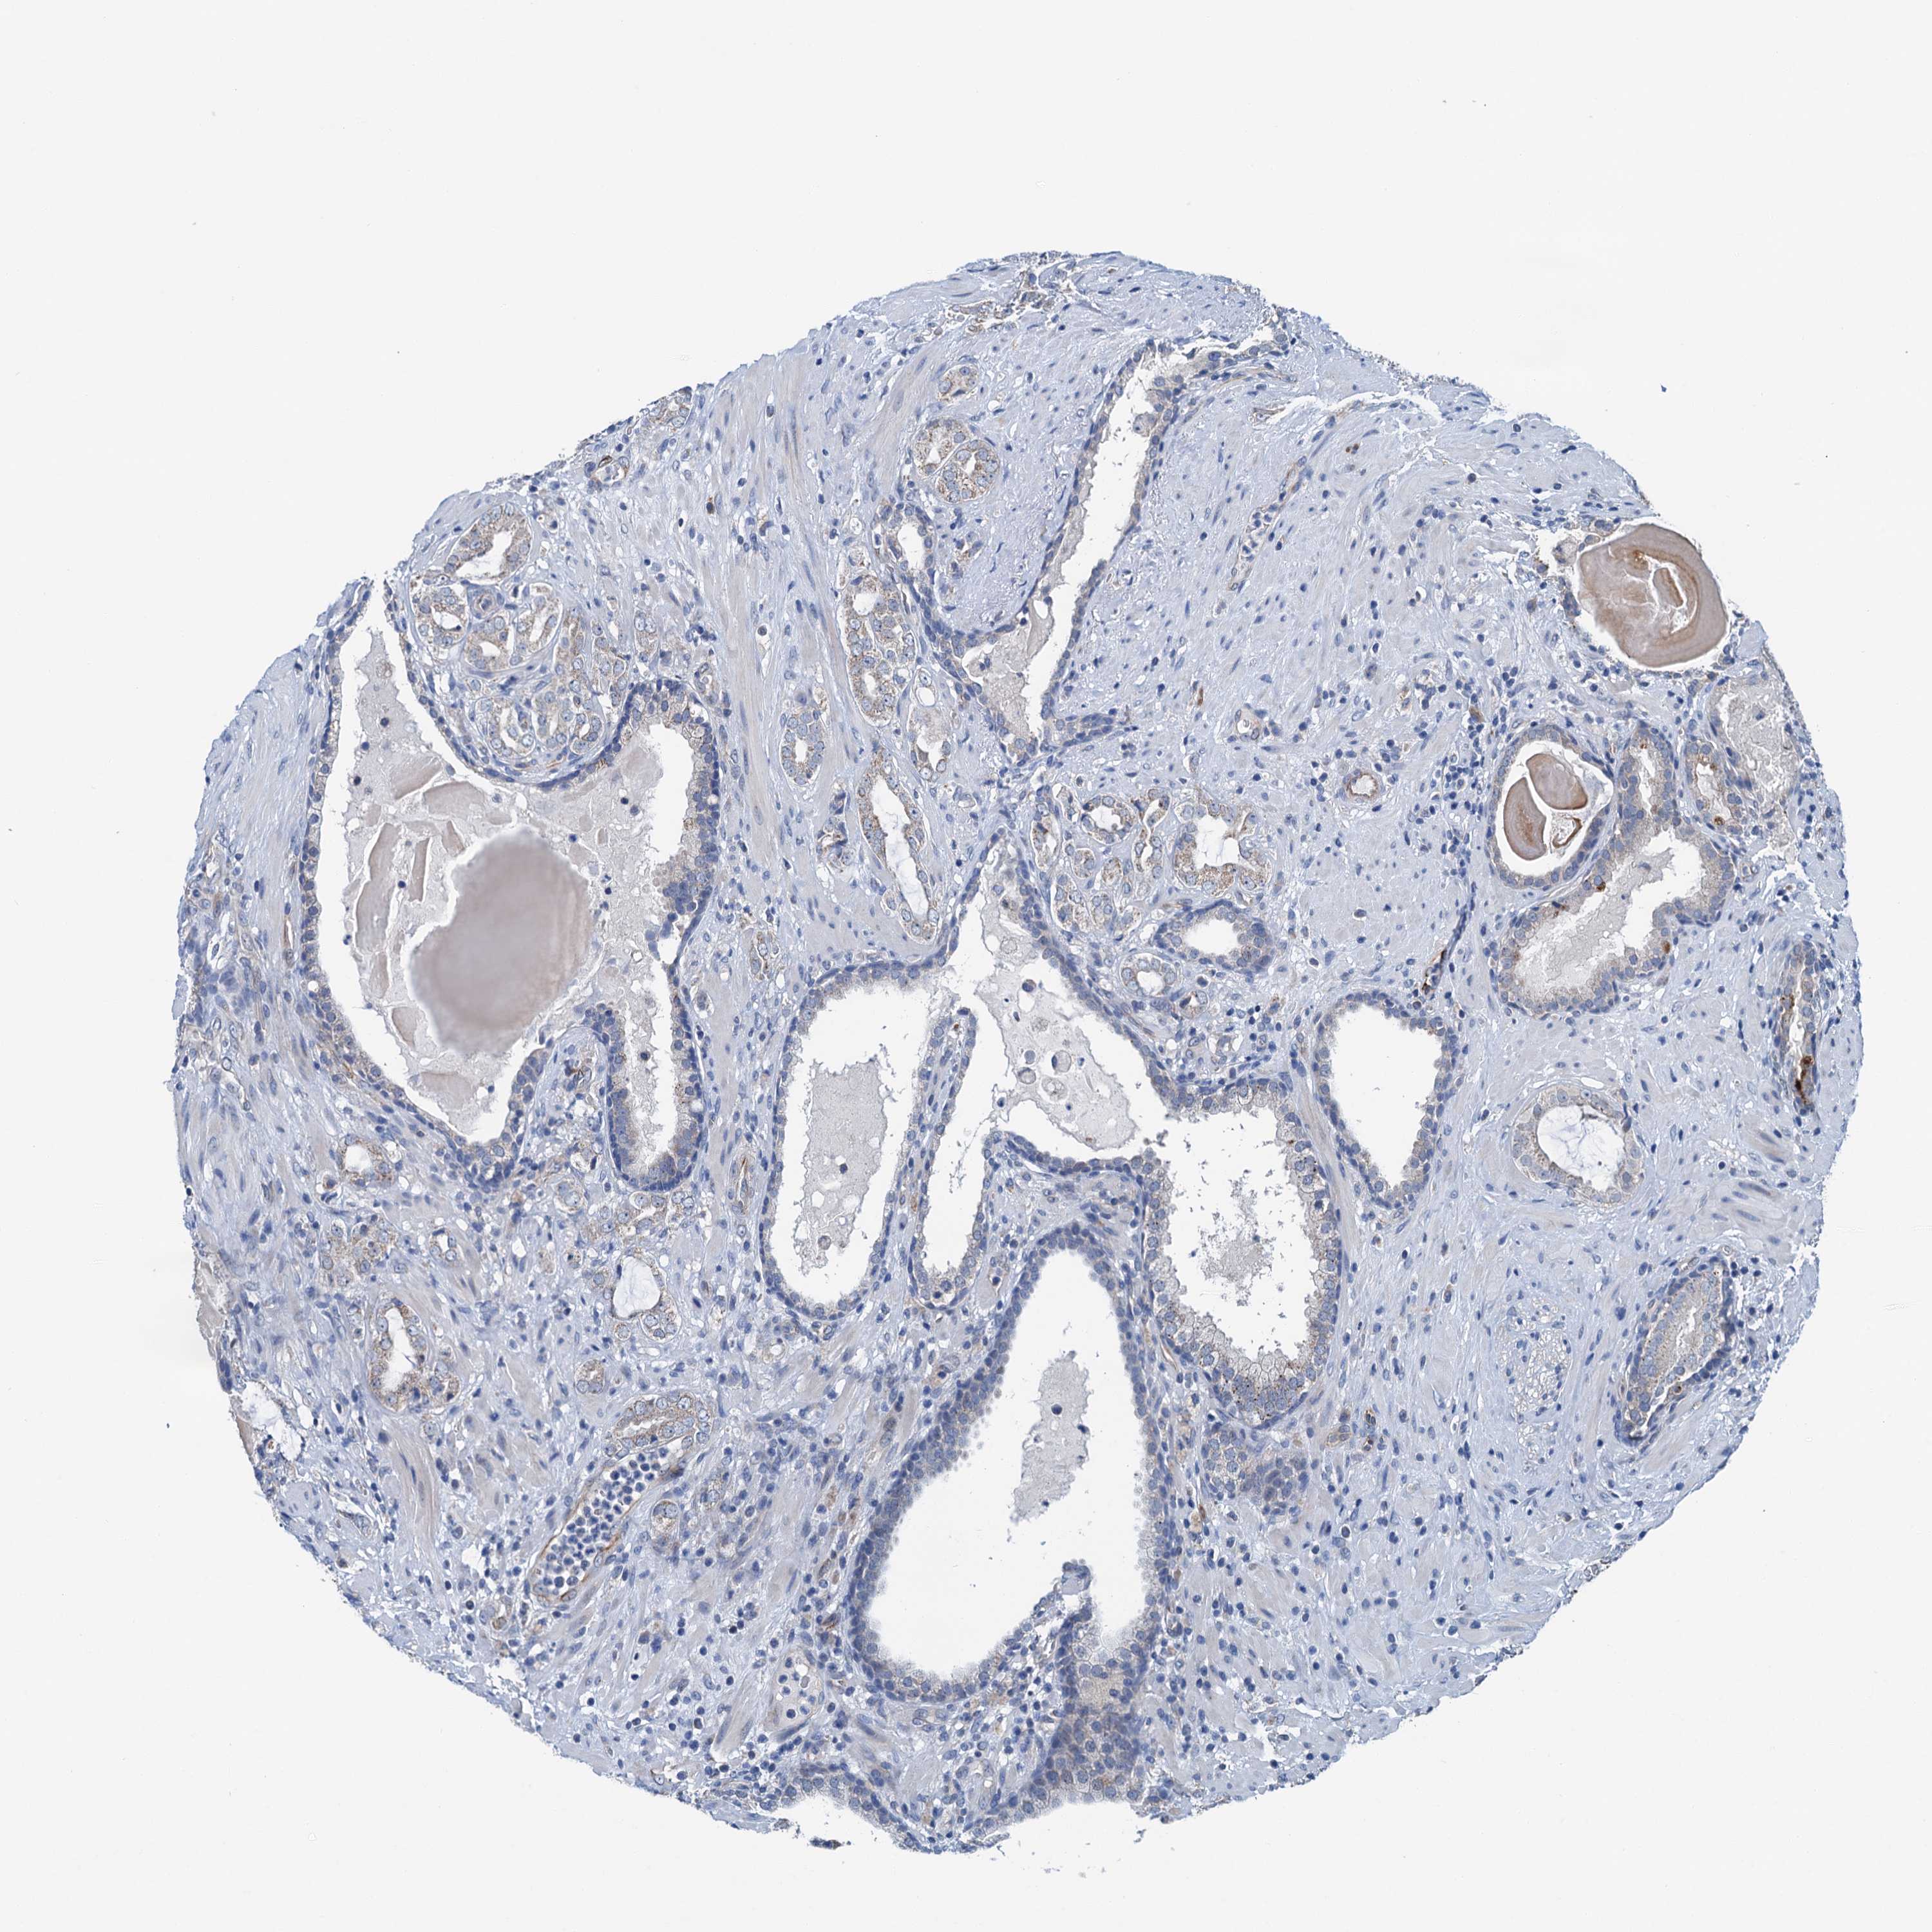

PROSTATE CANCER - Protein expressioni

A mouse-over function shows sample information and annotation data. Click on an image to view it in a full screen mode. Samples can be filtered based on level of antibody staining by selecting one or several of the following categories: high, medium, low and not detected. The assay and annotation is described here.

Note that samples used for immunohistochemistry by the Human Protein Atlas do not correspond to samples in the TCGA dataset.

Antibody stainingi

Antibody staining in the annotated cell types in the current human tissue is reported as not detected, low, medium, or high, based on conventional immunohistochemistry profiling in selected tissues. This score is based on the combination of the staining intensity and fraction of stained cells.

Each image is clickable and will lead to virtual microscopy that enables deeper exploration of all samples and also displays staining intensity scores, fraction scores and subcellular localization as well as patient and tissue information for each sample.

Antibody HPA040867

Staining

High

Medium

Low

Not detected

Intensity

Strong

Moderate

Weak

Negative

Quantity

>75%

75%-25%

<25%

None

Location

Nuclear

Cytoplasmic/membranous

Cytoplasmic/membranous,nuclear

Adenocarcinoma, NOS

Adenocarcinoma, High grade

Adenocarcinoma, Low grade